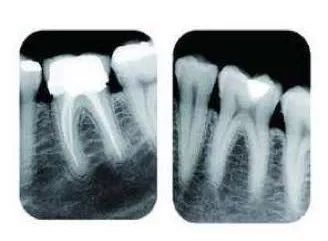

因此,如果牙齒出了問題,齒科醫(yī)生就需要有“透視”功能的X線片來檢查。通過x線片不僅能了解牙齒本身的病變情況,還可以了解牙根下有沒有囊腫、周圍骨頭有沒有吸收以及牙槽骨內(nèi)是否有埋伏牙、多生牙等。依據(jù)X線片綜合分析,可以提高齒科醫(yī)生診斷治療牙齒的準(zhǔn)確性和成功率。常見的牙科放射檢查包括曲面體層片( 全景片 )、小牙片、頭顱正側(cè)位片、全頭顱 CT、錐形束 CT( CBCT )等。由于牙齒下部隱藏在牙槽骨中,口腔醫(yī)生要了解牙齒的整體情況就需要拍攝全景片;要了解個別牙根及周圍變化,則選擇拍攝小牙片。醫(yī)生要判斷牙槽骨是否符合種植條件,或者了解埋伏阻生齒的三維位置以及其他頜骨內(nèi)病變組織的形態(tài)大小時,則需要進(jìn)一步拍攝 CBCT 。所以,拍牙片是一種幫助齒科醫(yī)生進(jìn)行診斷、治療、療效評估的重要手段,治療前用于發(fā)現(xiàn)病變程度、范圍;治療中用于引導(dǎo)治療、確定治療范圍和深度;治療后用于觀察療效。輻射分為電離輻射(如X光)和非電離輻射(如手機(jī)、微波爐),這里主要講述的是電離輻射。電離輻射的測量單位是西弗(Sv),但西弗是個非常大的單位,因此通常使用毫西弗(mSv)和微西弗(μSv),1Sv=1000mSv,1mSv=1000μSv)根據(jù)國際放射防護(hù)委員會(IRPA)提供的信息,每人每年受到的輻射劑量大約在2.5毫西弗左右,這個數(shù)值受地域緯度的影響而波動。其中大約80%來源于自然界,20%來源于人工輻射。而拍牙片是什么樣的輻射水平呢?根尖片為 5.2 μSv ,全口根尖片為 72.32 μSv ,曲面體層片為 10 ~ 23 μSv ,頭顱正位片為 1 ~ 5 μSv ,頭顱側(cè)位片為 1 ~ 3 μSv ,讓人「聞風(fēng)喪膽」的 CBCT 劑量一般也在 300 μSV 之內(nèi)。為了幫助大家更容易理解,我們用單位面積內(nèi)的香蕉數(shù)量表達(dá)輻射強(qiáng)度。之所以選擇香蕉,是因為香蕉富含鉀元素,天然鉀當(dāng)中約有0.0117%的放射性鉀——鉀40,而鉀40的半衰期長達(dá)12億5千萬年(地球歲數(shù)大約45億年)。